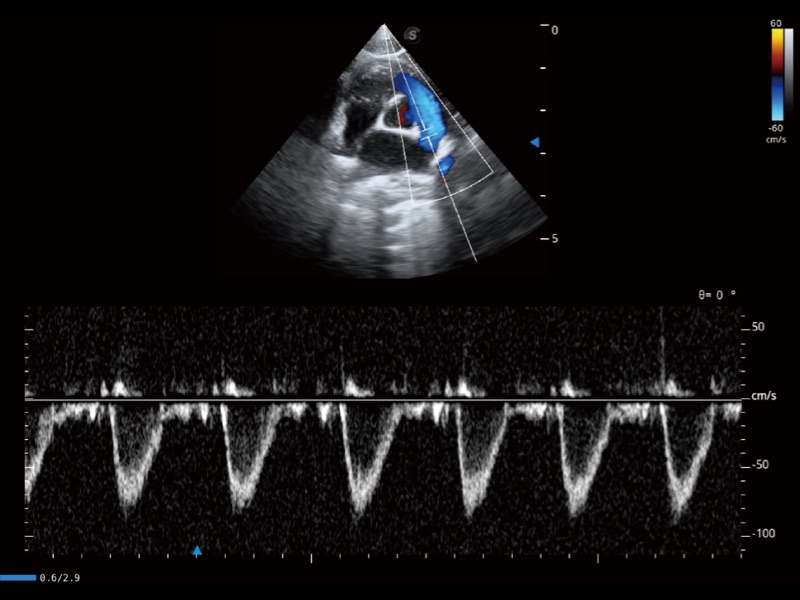

能够基于左心室壁追踪和辛普森法,自动计算射血分数,支持多个可移动点描迹,与手动测量相比,极大节省了动物医生的时间和精力。

通过360度任意调节3条M型取样线,在同一心动周期上观察心脏不同位置的运动曲线,得到准确的心功能测量数据,有效评估心肌运动及左心室功能。

当心脏测量结果超出正常范围时,可实时预警提示动物医生,减少疾病漏诊概率。